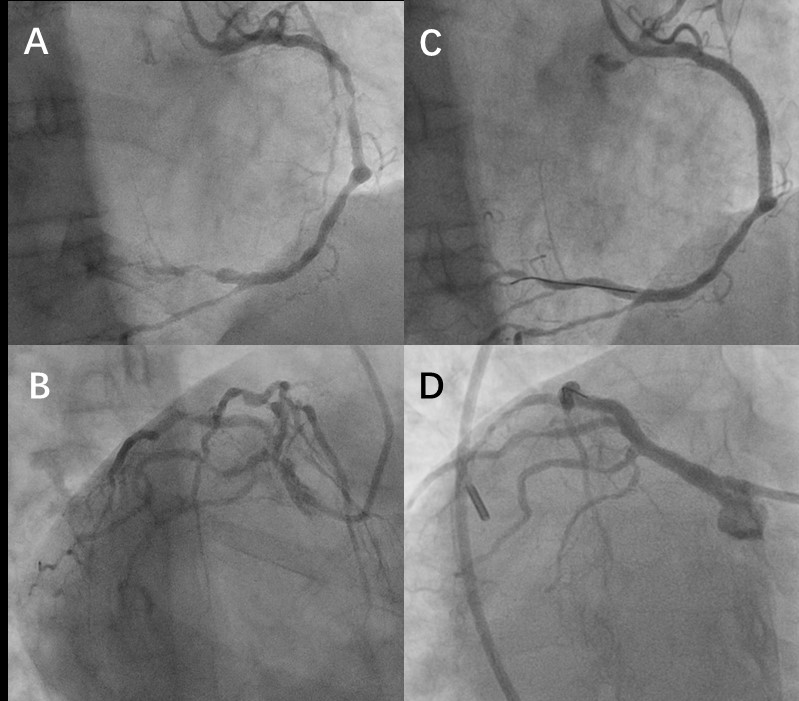

A、B:术前右冠及左冠;C、D:血运重建后右冠及左冠。

入院时,心内科急诊介入团队立即给刘阿姨做了冠脉造影检查,发现其右位心,右冠原支架内狭窄95%,左主干尾部狭窄90%伴斑块破裂影,同时前降支和回旋支都存在80-90%的严重狭窄。

患者病情危重、命悬一线,然而先天性心脏位置畸形给原本就复杂的手术操作带来了新的难题。心内三科主任潘宏伟团队立即对刘阿姨的情况进行讨论,制定了针对镜像心的手术方案,为其实施了急诊支架植入术。术中,由于刘阿姨的心脏及冠脉左右翻转,给手术入路及导丝通过等手术操作带来了一定困难。心脏介入手术的机器设置是按照心脏在病人左侧设计的,并且术中的操作也与医生的平时习惯完全相反,明显增加了手术的风险和难度,可以说是“难上加难”。最终在主动脉球囊反搏(IABP)辅助及冠脉血管内超声(IVUS)精准定位下,潘宏伟主任团队选择经右腿动脉入路,反向操作,成功完成了右冠及左主干到前降支的血运重建,刘阿姨最终转危为安,于4月27日出院。